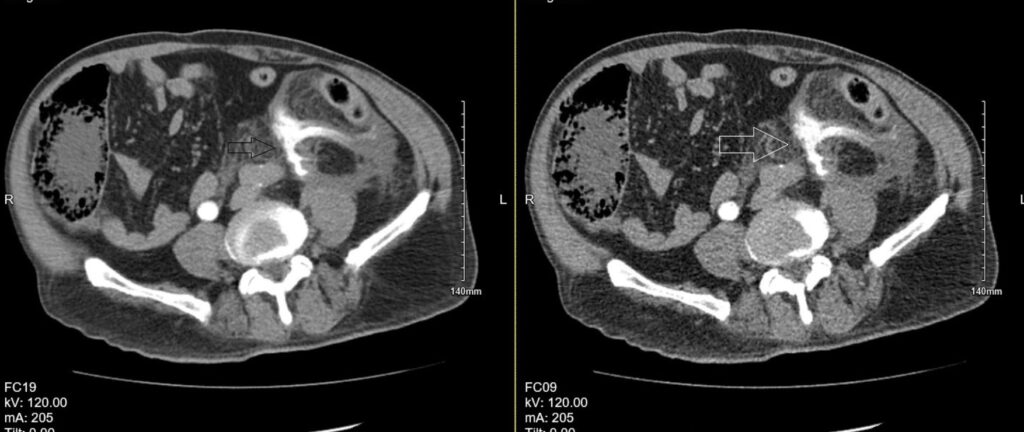

On arrival to Emergency department, patient was complaining of severe lower abdominal pain. On examination, he was apyrexial, tachycardiac 109 per minute and tachypnoeic 24 per minute. His lower abdomen was tender on palpation. His lactate was 3.99 mol/L, white blood cells count of 17.3 and C reactive protein of 31. A bed side urinary bladder ultrasound scan revealed 10 ml volume. He was commenced on sepsis six bundle. His case was discussed with Urology department in a tertiary referral centre. They advised to do a CT Urogram with query of bladder perforation. CT Urogram with contrast revealed left ureter rupture with contrast extravasation and retroperitoneal haematoma (figure 1).

Figure 1. Contrast-enhanced CT demonstrating rupture of the left ureter with active contrast extravasation and associated retroperitoneal haematoma.